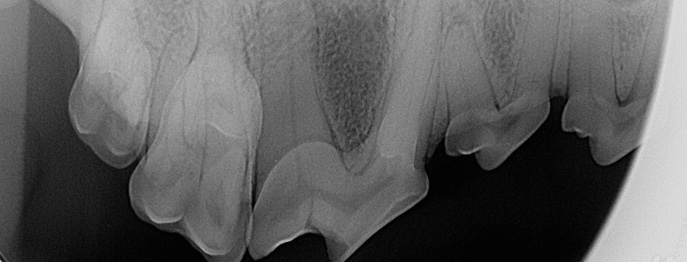

Zahn-Fälle mit Fokus Röntgeninterpretation (NUR LIVE!)

In diesem interaktiven vetinar sollen möglichst viele unterschiedliche dentale Röntgenbilder und Fälle (teilweise auch mit CBCT) besprochen werden. Hierzu wird eine Vielzahl typischer und auch untypischer Fälle von Hund und Katze gezeigt.

Da das Augenmerk auf der Bildbefundung liegen soll, können keine Detailbesprechungen der Therapie und des Outcomes vorgenommen werden - auf diese wird kurz eingegangen.